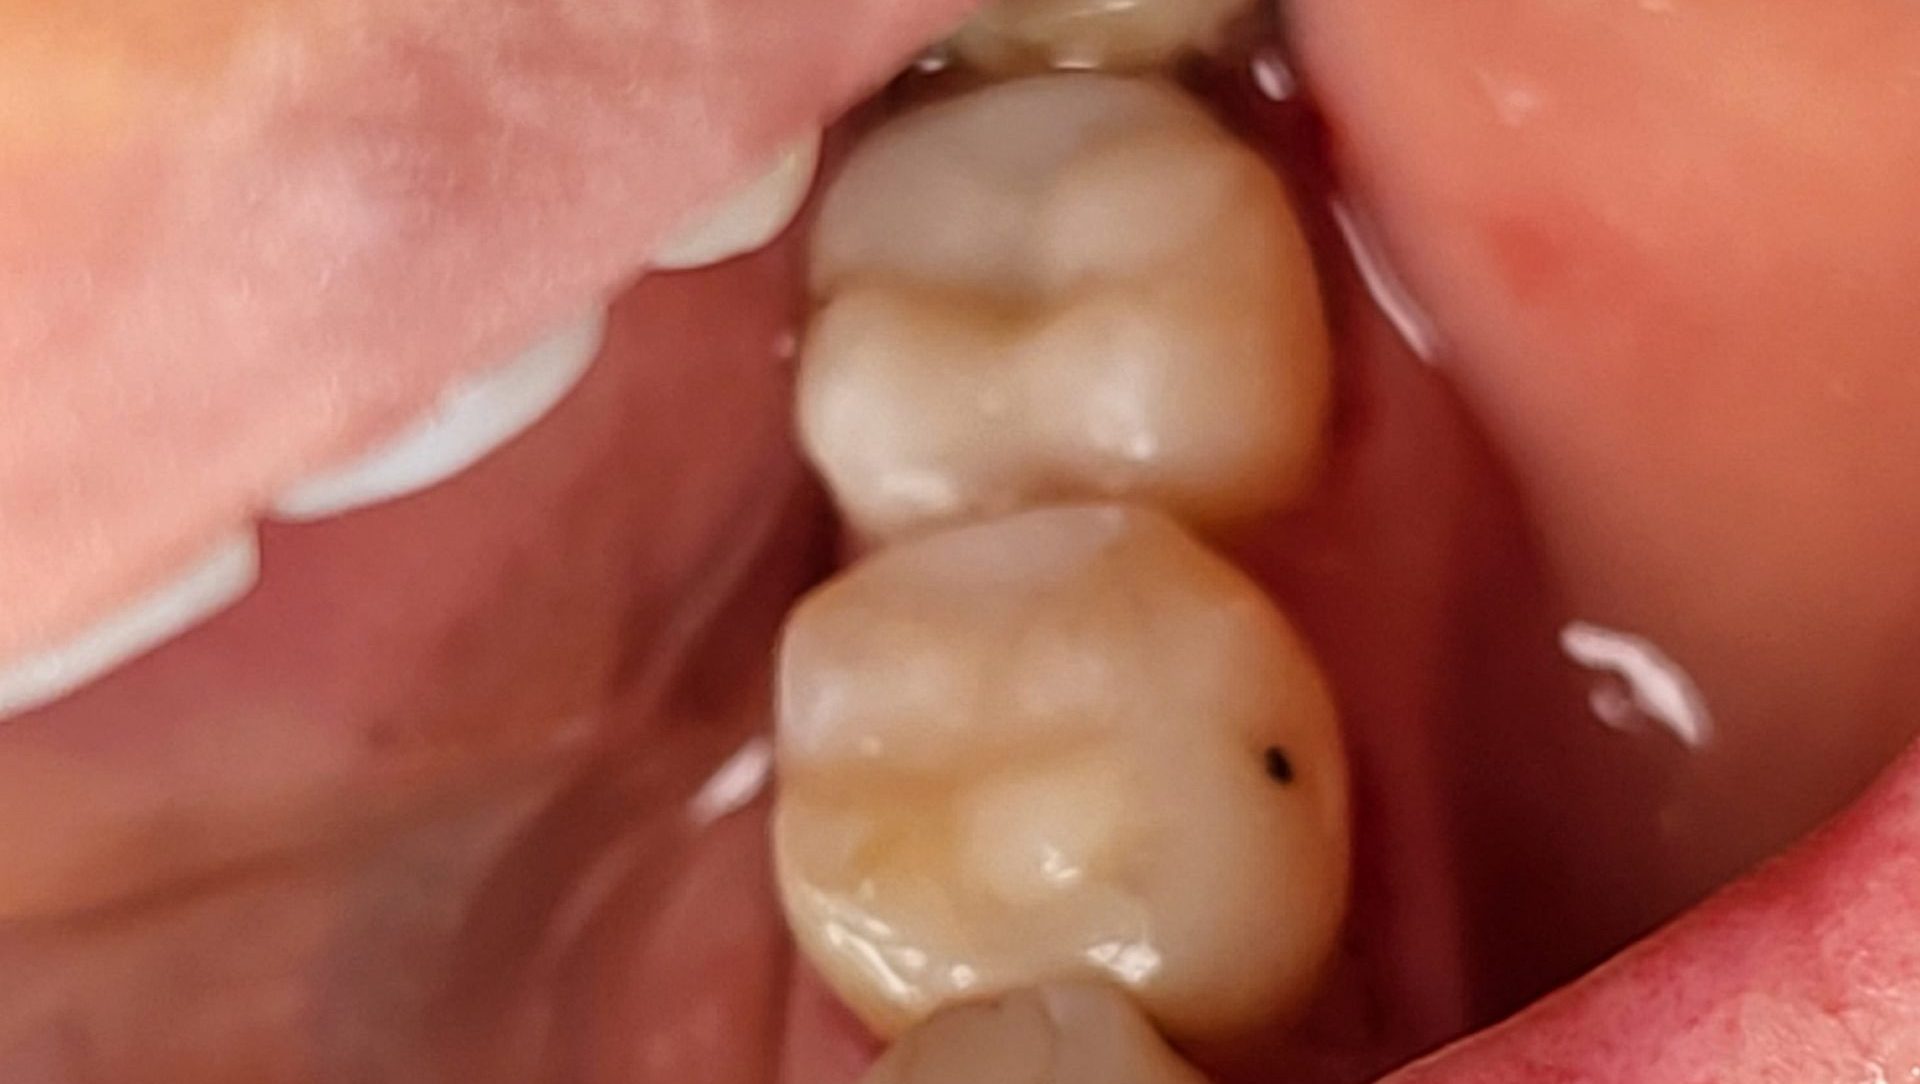

Dijital İnley-Onley

Çürük boşluğunun dijital kamera ile görüntüsü alınarak tek randevuda bilgisayar ile üretilen porselen dolgudur.